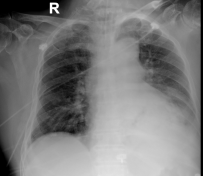

10-25胸部X线